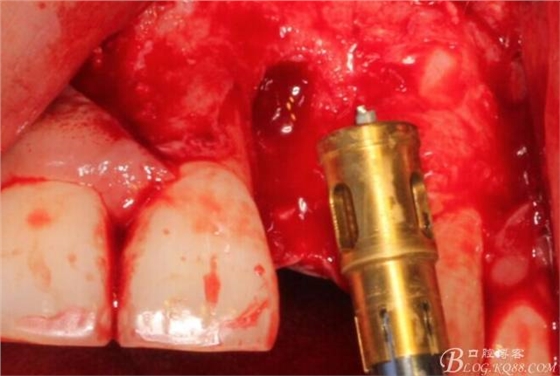

根方用取骨鉆取自體骨。

旋入一長(zhǎng)兩短3顆鈦釘。